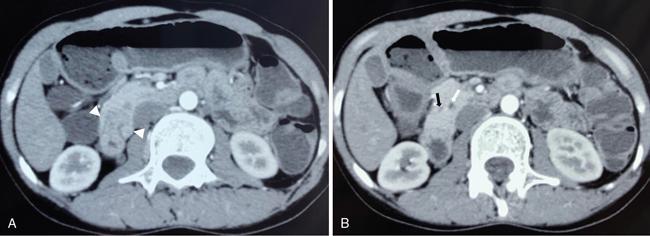

Priscilla Joshi, Mangal Subhash Mahajan, Vandana Jahanvi Imaging is important in paediatric patients with pancreatic pathologies which can be congenital, pancreatitis or neoplastic. Congenital pancreatic anomalies predispose the children to recurrent attacks of pancreatitis and other complications. Paediatric pancreatic tumours are uncommon but when they do occur imaging is essential for their diagnosis, staging and posttreatment follow-up. Pancreas divisum is the most common congenital pancreatic anomaly. It occurs in approximately 4%–14% of population. Failure of fusion of dorsal and ventral pancreatic ducts results in pancreatic divisum. Three variants of pancreatic divisum are known: In most cases, pancreatic divisum is asymptomatic. However, it may give rise to recurrent episodes of pancreatitis. Pancreatitis is believed to occur due to inadequate drainage of pancreatic secretions by the duct of Santorini. Pancreatic divisum is easily identified on MRCP (magnetic resonance cholangiopancreatography) which is a noninvasive technique and therefore is now increasingly being performed over ERCP to avoid ERCP-induce pancreatitis. Secretin-induced MRCP improves the visualization of the pancreatic ducts. The dorsal duct can be seen passing the CBD anteriorly and superiorly on imaging. This entity can also be identified on MDCT if the pancreatic duct is visualized. Rarely, it may be associated with cystic dilatation of terminal portion of duct of Santorini which is called Santorinocele. Failure of rotation of ventral bud along with the duodenum results in encasement of duodenum by a rim of pancreatic tissue and this entity is known as annular pancreas. The band of pancreatic tissue encircling the duodenum could either completely or partially surround the duodenum and is in continuity with pancreatic head. It occurs in approximately 1 in 20,000 population. Not all cases of annular pancreas present in childhood. In paediatric age group, it can present as neonatal duodenal obstruction because of associated duodenal stenosis. Children and adults with annular pancreas may also present with recurrent pancreatitis, postbulbar duodenal ulcerations or biliary obstruction. On upper gastrointestinal studies (barium meal), characteristic narrowing of second part of duodenum is seen. CT and MRI may show rim of pancreatic tissue encircling the duodenum. In partial annular pancreas (Fig. 9.16.2), pancreatic tissue is seen extending posterolateral or anterolateral to the duodenum with the pancreatic tissue giving a ‘crocodile – jaw’ configuration. This in the presence of gastric outlet obstruction helps in the diagnosis of incomplete annular pancreas. MRCP shows the pancreatic duct encircling the second part of the duodenum and entering it over its right lateral aspect. The pancreatic duct draining the annular segment usually drains into the main pancreatic duct. It can also drain into the intrapancreatic portion of common bile duct, the duct of Wirsung or the duct of Santorini. Secretin-induced MRCP because of its ability to demonstrate ductal anatomy well may become the best noninvasive imaging modality for diagnosis of pancreatic ductal variants including annular pancreas. Other causes of paediatric duodenal obstruction should be kept in mind while diagnosing annular pancreas. Other than annular pancreas, the presence of duodenal narrowing on barium study in neonates, should raise the possibilities of duodenal atresia, duodenal web and Ladd’s bands. In duodenal atresia, the contrast does not pass beyond the obstruction and no air is seen on radiograph beyond the atretic segment. Whereas, in annular pancreas, intestinal gas is seen distal to the involved segment. And on upper gastrointestinal studies, the duodenal bulb is distended with slow transit of oral contrast through the stenosed duodenal segment distally. In duodenal web classical ‘wind–sock’ diverticulum is seen due to distal stretching of the web forming an intraluminal pseudodiverticulum. On barium studies, thin radiolucent membrane is seen due to filling of barium within the lumen and around the diaphragm. The mutation in the developmental protein IPF1, results in pancreatic agenesis. It is very uncommon as it is incompatible with life. Anomalies associated with this condition are: foetal growth restriction, agenesis of gallbladder and polysplenia. Hypoplasia or partial agenesis occurs due to nondevelopment of dorsal or ventral pancreatic bud. Partial agenesis of the dorsal pancreas is more common than agenesis of the ventral portion. However, complete dorsal pancreatic agenesis is rare. Dorsal pancreatic agenesis is often associated with heterotaxia syndrome. Partial dorsal pancreatic agenesis is more common than partial ventral agenesis. Complete dorsal pancreatic agenesis is however rare. In partial dorsal agenesis, short rounded head of pancreas is seen adjacent to the duodenum with absence of pancreatic neck, body and tail; however, remnant of duct of Santorini and minor duodenal papilla are generally present. In complete dorsal agenesis, both the minor duodenal papilla and the duct of Santorini are absent. The distal pancreas contains the islet cells, hence those with dorsal agenesis are at a higher risk of developing Diabetes Mellitus. This uncommon condition is diagnosed when there is an accessory lobe of pancreatic parenchyma originating from the main gland and draining through an aberrant duct. The accessory lobe may be of varying size and may drain into the main pancreatic duct through a narrow or a wide communication. Association with gastric duplication cyst is known and if present the aberrant duct communicates with the gastric duplication cyst and the main pancreatic duct. Accessory pancreatic lobe may present as acute pancreatitis which is believed to result from obstruction of the pancreatic duct by viscus secretions, ulcer bleeding or biliary sludge. Ectopic pancreatic tissue can be seen in 0.6%–13.7% of population. It is most commonly seen in the stomach or duodenum. The ectopic tissue is generally located in the submucosa. Although, usually asymptomatic, it presents as stenosis, ulceration, gastrointestinal haemorrhage or intussusception. Pancreaticobiliary maljunction is a congenital abnormality in which the main pancreatic and common bile ducts join outside the duodenal wall that forms a common channel. It was first described by Arnolds in 1906. Women are more frequently affected than men with a female to male ratio of 3:1. It is predominantly present in young women. Its incidence is 0.9%–6.2% on ERCP and 61.8%–70% on autopsy. Although few familial cases have been reported whether pancreaticobiliary maljunction is hereditary remains unclear. It is diagnosed on the basis of radiological findings or anatomical findings at surgery or autopsy. Hence, radiologist play crucial role in making diagnosis of this entity. Pathogenesis of pancreaticobiliary maljunction is controversial. Several studies have proposed that anomalous development of the ventral pancreas with abnormal fusion between the bile duct and branches of the ventral pancreatic duct is responsible for development of pancreaticobiliary maljunction. Normally, the main pancreatic duct and common bile duct open either separately or join to form a common channel that opens in second part of duodenum. Length of the common channel varies between 1 and 12 mm normally. Sphincter of Oddi is present at the distal end of pancreatic and common bile ducts. It regulates outflow of pancreatic and bile juice. The sphincteric control at the pancreaticobiliary junction is important for the regulated drainage of bile and pancreatic juice. In maljunction, as the union of the bile duct and the pancreatic duct is outside the duodenal wall, the sphincter of Oddi is unable to regulate the flow of pancreaticobiliary juices resulting in bidirectional regurgitation of juices (Graphic 9.16.1). It produces various pathological conditions in the biliary tree and pancreas. On the basis of dilatation of common bile duct, pancreaticobiliary maljunction is divided into that with biliary dilation and without biliary dilatation. The former is more common and present in 77% of cases. The latter is less common and present in remaining 23% of cases. New Komi classification (Graphic 9.16.2) is based on how the pancreatic and common bile ducts join. It takes into account presence or absence of the common channel dilatation and the concept of pancreatic divisum. Type I union is bile duct type, in which the common bile duct joins the pancreatic duct at right angle. It has single papilla. It is subclassified into type IA and IB based on absence or presence of the common channel dilatation respectively. Type II union is pancreatic duct type, in which the pancreatic duct joins the common bile duct at an acute angle. It also has single papilla. It is subclassified into type IIA and IIB based on absence or presence of the common channel dilatation, respectively. Type III is complex type, in which the two ducts join in complex configuration. It has two papillae. It is subclassified into type IIIA, IIIB and IIIC. Type IIIA is similar to pancreatic divisum with biliary dilatation. Type IIIB is characterized by absence of duct of Wirsung. Type IIIC is further subclassified into IIIC1, IIIC2 and IIIC3. A thin communicating duct between the main and accessary ducts is present in type IIIC1. A common channel is made up of common and accessary ducts of equal calibre in type IIIC2. There is complex network of enlarged ducts that join each other by total or partial dilatation of the ductal system in type IIIC3. Japanese Study Group on Pancreaticobiliary Maljunction proposed a new classification (Graphic 9.16.3) in 2015 on the basis of formation of pancreaticobiliary maljunction. According to this new classification, pancreaticobiliary maljunction is divided into four types: (1) Stenotic type: The common channel is joined by the distal CBD with stenosis, (2) Nonstenotic type: The common channel is joined by the distal CBD without stenosis, (3) Dilated common channel type: As the name suggests, the common channel is dilated and (4) Complex type: A complicated pattern is formed by the pancreaticobiliary junction. Pancreaticobiliary maljunction with congenital biliary dilatation have higher incidence of symptoms in neonatal and infantile period and manifest as jaundice and abdominal mass. Less common symptoms include abdominal pain, vomiting and fever. Dilatation of common bile duct is an important finding on ultrasonography and further imaging with magnetic cholangiopancreatography is recommended to look for the status of common channel. Pancreaticobiliary maljunction without congenital biliary dilatation is more difficult to diagnose because of less frequent symptoms and less remarkable imaging findings. These patients are frequently asymptomatic but may presents as abdominal pain and hyperamylasaemia in adulthood. Many adult patients may show signs of biliary cancers. Focal or diffuse gallbladder wall thickening may be an early clue for the diagnosis. Hence, pancreaticobiliary anatomy should be assessed by magnetic resonance cholangiopancreatography when no specific cause of gallbladder wall thickening is established. The diagnosis of pancreaticobiliary maljunction is made when there is an abnormally long common channel of the pancreatic duct and the CBD; or there is an abnormal union between the pancreatic and bile ducts seen on an investigation which directly images these structures. These include endoscopic retrograde cholangiopancreatography, percutaneous transhepatic cholangiography or intraoperative cholangiography, magnetic resonance cholangiopancreatography or three-dimensional drip infusion cholangiography computed tomography (CT). However, when the common channel is relatively short, it is crucial to confirm that the effect of the papillary sphincter does not extend to the junction with direct cholangiography. There is no clear definition of a long common channel. Few authors suggest 8 mm or longer while others suggest 15 mm or longer as a long common channel. It can also be diagnosed if the pancreaticobiliary junction is demonstrated outside the duodenal wall on endoscopic ultrasound or multiplanner reconstruction images of multidetector-row CT. Pancreaticobiliary junction must be present outside the duodenal wall or the union of pancreatic or bile duct must be abnormal at surgery. Elevated amylase levels in the bile within the bile duct and gallbladder obtained immediately after laparotomy and presence of extrahepatic biliary dilatation strongly suggest the existence of pancreaticobiliary maljunction. Rarely, the amylase levels are close to or below the normal serum value in these patients. When cystic, fusiform, or cylindrical dilation is present in the extrahepatic bile ducts, detail workup is necessary to determine whether pancreaticobiliary maljunction is present. To diagnose biliary dilatation, maximum calibre of the common bile duct is measured. Diagnosis of bile duct dilatation is age-dependent (Table 9.16.4). Ultrasound is used as screening tool and alone may not be enough to detect an anomalous pancreaticobiliary junction. Extrahepatic bile duct dilation or gallbladder wall thickening are the clues to make early diagnosis of pancreaticobiliary junction. Endoscopic ultrasound demonstrates the pancreatic and bile duct junction outside the duodenal wall and help to diagnose pancreaticobiliary maljunction. Magnetic resonance cholangiopancreatography is an accepted noninvasive imaging tool to demonstrate the pancreaticobiliary anatomy. It is preferred over ERCP. Source images and maximum intensity projection images of 3D MRCP are very useful to delineate the pancreaticobiliary anatomy. Its sensitivity is 75% in adult and 44%–65% in children. Fig. 9.16.3 shows a case of Pancreaticobiliary maljunction with Choledochal cyst. Secretin-stimulated dynamic MRCP and time-spatial labelling inversion pulse (Time-SLIP) can be used to identify the pancreaticobiliary reflux. Secretin stimulates the exocrine pancreas to secrete fluid. This increase of fluid content within the lumen of pancreatic duct improves visualization. In pancreaticobiliary maljunction, there is enlargement and retrograde increase in signal intensity of the common bile duct. Time-SLIP MRI allows direct visualization of pancreaticobiliary flow by placing the inversion pulse at the head and body of pancreas and suppressing the background. Gadoxetic acid-enhanced MRI is used to identify biliopancreatic reflux. Gadoxetic acid is a hepatobiliary specific contrast agent. It is taken up by hepatocytes and excreted into the bile. In pancreaticobiliary maljunction, there is retrograde increase in signal intensity of the pancreatic duct. Multiplanar reconstruction images of the contrast-enhanced high-resolution multidetector CT scan can demonstrate the communication of the pancreatic and bile ducts and help to diagnose pancreaticobiliary maljunction. Its sensitivity is 58%–100% in adults and 20% in children. Drip infusion CT cholangiography involves intravenous injection of biliary contrast agent. It demonstrates details of pancreaticobiliary anatomy; however, it sometimes fails to demonstrate the pancreatic duct preventing the diagnosis of pancreaticobiliary anatomy. Endoscopic retrograde cholangiopancreatography confirms lack of effect of the sphincter of Oddi on the pancreatic and bile duct junction. Its sensitivity is 75%. Main advantage of ERCP is that it allows bile and tissue sampling and therapeutic procedures. In pancreaticobiliary maljunction, the Oddi sphincter fails to regulate the pancreaticobiliary junction. Normally, hydrostatic pressure within the pancreatic duct is higher than that in the bile duct. Hence pancreatic juice often refluxes into the bile duct. There is increased pressure in the bile and pancreatic duct secondary to obstruction of the common channel or primary stricture of distal bile duct. Obstruction or stricture is caused by impaction from a protein plug. It is often a temporary process because these protein plugs are fragile and resolve spontaneously. It causes transient and intermittent symptoms like abdominal pain, vomiting, and jaundice. Protein plugs consist of lithostathine. It is a soluble protein secreted by pancreas. They are often depicted at ERCP but not at CT or MRCP. Incidence of acute pancreatitis in pancreaticobiliary maljunction is 30% in children and 9% in adults. Chronic pancreatitis is present in 3% of these patients. In majority, the changes are less severe but can be recurrent. Protein plugs are believed to be one cause of acute pancreatitis. Pancreatic calcifications are usually absent in chronic pancreatitis with pancreaticobiliary maljunction. Common bile duct and gallbladder calculi occur more often in adults than in children. Its incidence is 23% in adults and 9% in children. Calculi formation appears to be related to bile stasis because pigmented calculi are more commonly detected than cholesterol calculi in patients with pancreaticobiliary maljunction.

Imaging findings